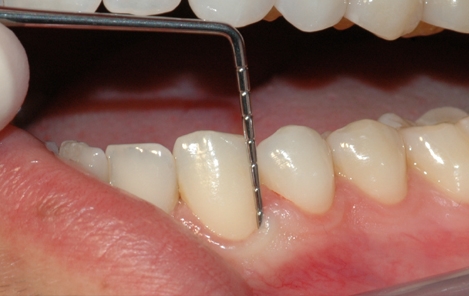

Tannlegen undersøker hver enkelt tann etter hull og skader

Tannkjøttet og tennenes benfeste blir vurdert